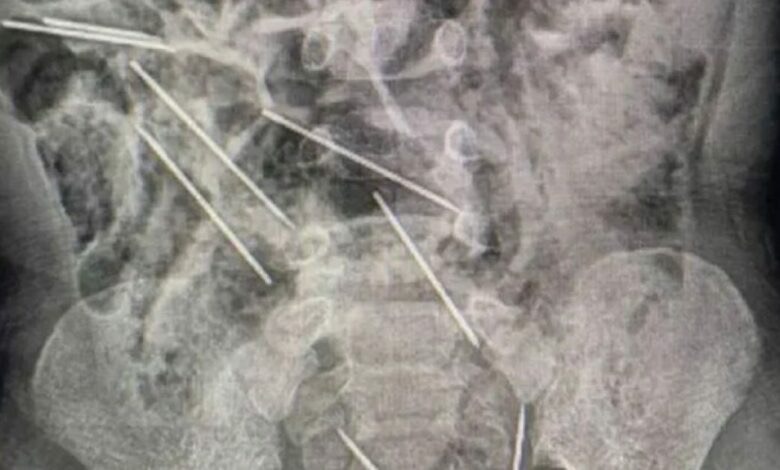

Dyvjeçari në Peru gëlltiti tetë gjilpëra, mjekët arrijnë ta shpëtojnë

Mjekë në veriperëndim të Perusë, kanë arritur t’i shpëtojnë jetën një djali dyvjeçar që kishte gëlltitur tetë gjilpëra medicinale.

“Kur u futëm në sallën e operacionit dhe i hapëm barkun, zbuluam objekte të metalta dhe e kuptuam se bëhet fjalë për gjilpëra”, tha mjeku Efrain Salazar, transmeton Telegrafi.

Mediat lokale raportojnë se bëhet fjalë për gjilpëra të injeksioneve, me të cilat vaksinohen kafshët në fermën në të cilën punon e ëma e vogëlushit.